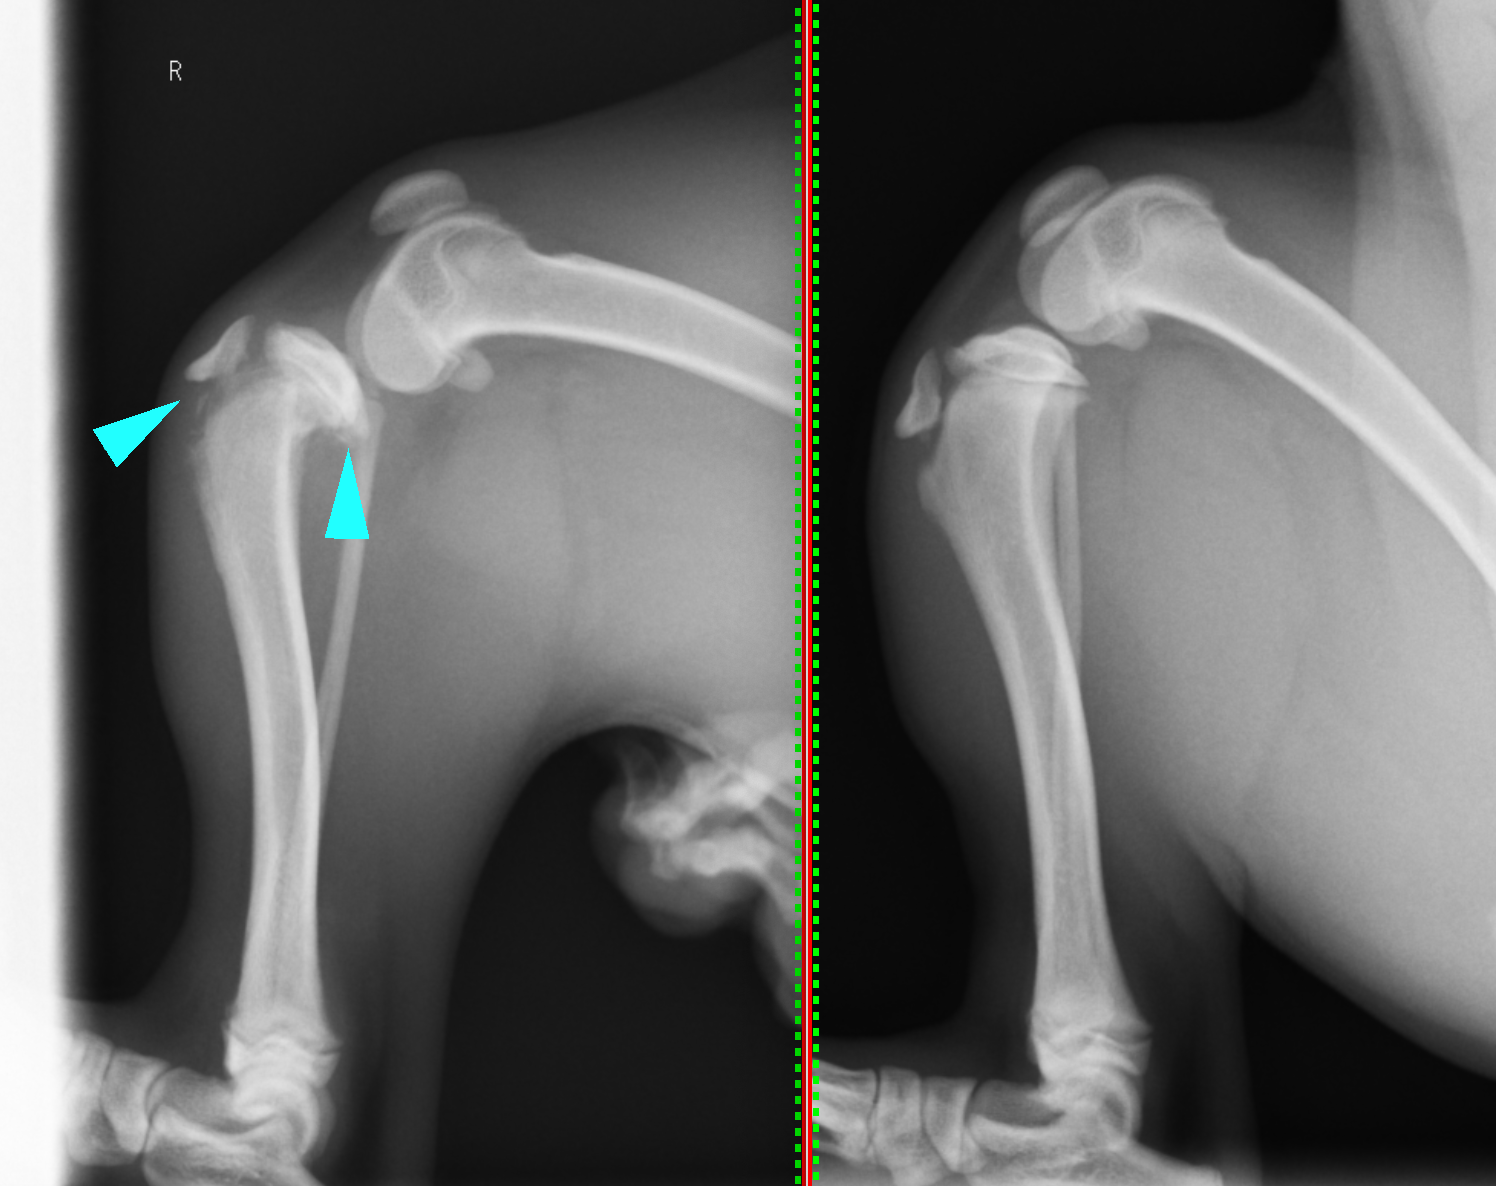

触診上右後肢の筋肉量の低下が認められ、X線画像検査を行うと脛骨近位が骨折しているのが確認されました。

左の画像が患肢で、右は反対の正常肢です。成長板とよばれる少し黒っぽいところで、矢印の部分が右側にずれてしまっているのが確認できます。

脛骨近位は血流が豊富で、特に若齢では癒合が早いため、このずれた状態のまま放っておくとその形で癒合してしまい(変形癒合)、足を着くことができなかったり、後々に前十字靭帯断裂などの重大な合併症を引き起こしてしまいます。そのため、なるべく早期に手術を行い、ずれた骨を正しい位置に戻し固定することが重要となります。